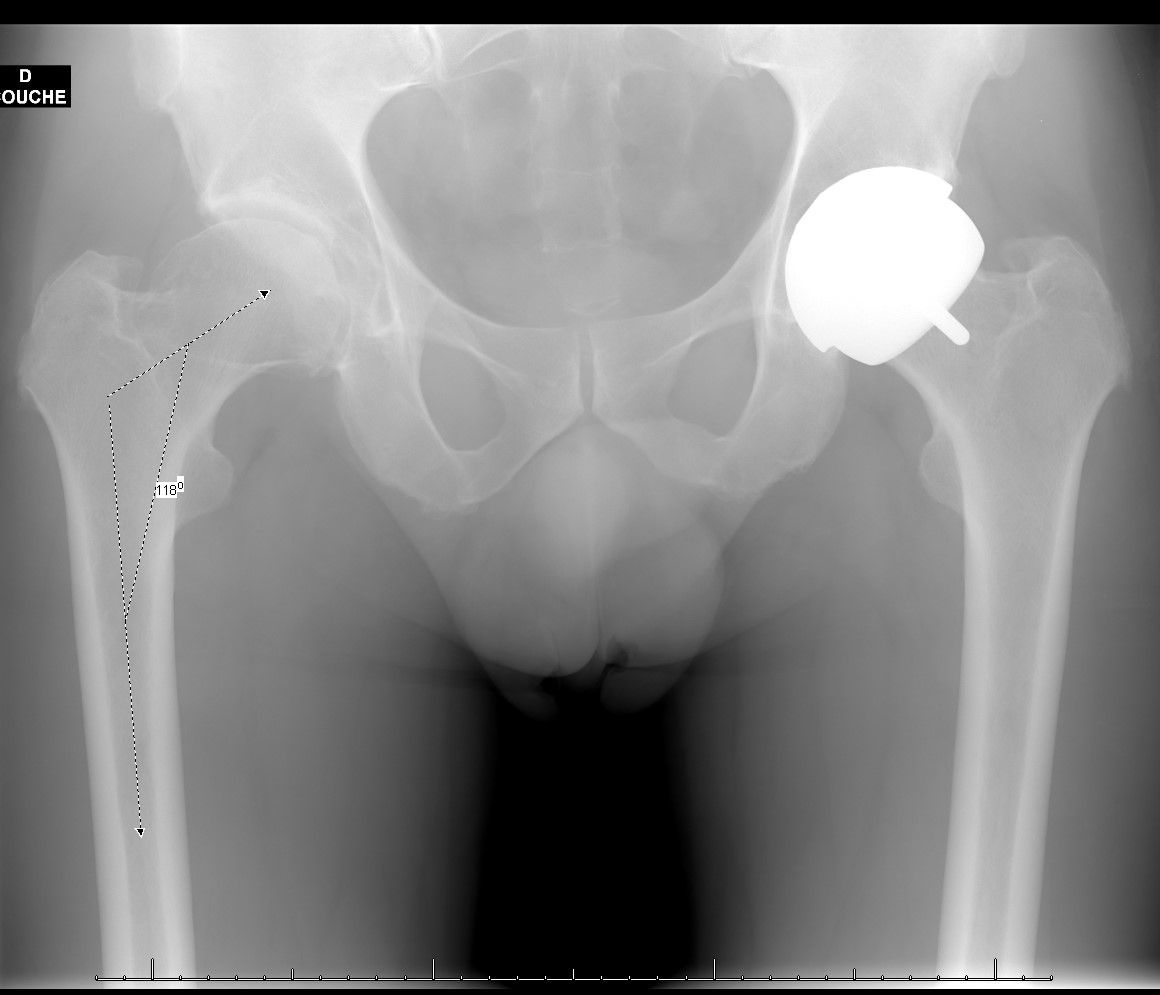

All patients underwent a preoperative and final clinical evaluation including Devane, Postel Merle d'Aubigné (PMA) and Harris Hip Score. Global and sectoral joint ranges were recorded. Radiographic analysis was performed on a front view of the pelvis, with the limb internally rotated by 15 to 20°. Interpretation and reproducibility of the radiographic analysis between the postoperative and preoperative films was ensured by measuring pelvic tilt and rotation. Criteria for reproducibility of the images were used with the tip of the coccyx, which was considered centred if it was located between 2 and 4 cm from the pubic symphysis. This ensured that there was no significant variation in version and/or pelvic tilt. The neck/shaft angle was measured between points C, C', and D, where C is the centre of the femoral head, C' is the middle of the neck, and D is the middle of the femoral shaft. The femoral offset was measured as the perpendicular to the femoral shaft axis through point C. The Stem Shaft Angle (SSA) was measured on the recoil films by considering the axis of the femoral implant in relation to the cervical axis. If the implant was deviated from the femoral neck, this was indicated by a + in degrees (°), and if it was deviated, by a - in °.

The mean preoperative neck/shaft angle was 120.9° [114.7-125]. The mean femoral offset decreased from 53.8 mm [40.9-75] preoperatively to 52.3 mm [40-70] at follow-up, and this difference was not significant (p> 0.05, Table 2).

The femoral offset was thus reduced by an average of 1.6 mm (6.7/-7.8), without this reduction being significant. The SSA angle at follow-up was 131.3° [118-134]. The mean valgus gain of the femoral implant compared to the native CCD bone angle was 8.7° (-4.6/14.8) (p<0.0001). Compared to preoperative data, four patients were elongated by less than 5 mm. No dislocations or thromboembolic events were observed. No hips were revised at the longest follow-up and we did not observe any Adverse Reaction to Metal Debris complications.